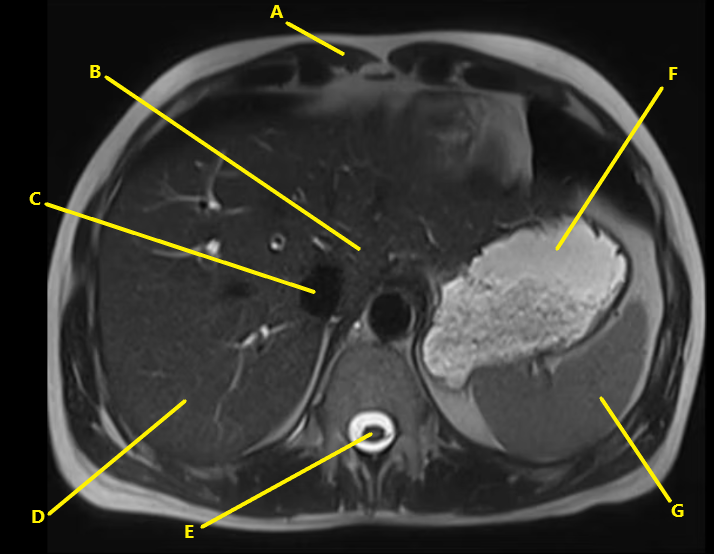

What is letter G ?